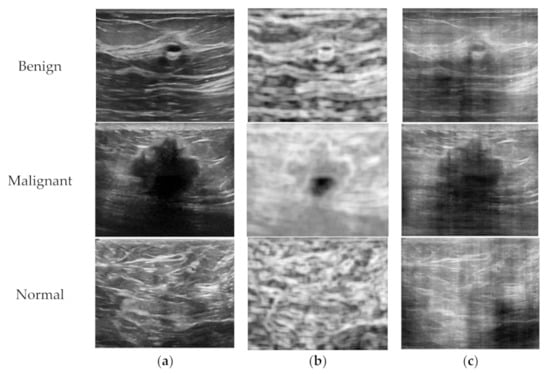

In this study, we proposed one possible way for increasing the number of training data for two feature maps in order to extract (or abstract) its own feature more exactly. Since two feature maps were calculated from a B-mode image, the extended feature maps could be generated using various sizes of filters or different signal processing techniques. For the entropy images, three more sizes of entropy filters which are 9 × 9, 15 × 15, and 31 × 31 pixels, in addition to the entropy filter of 25 × 25 pixels, were applied to calculate new entropy images in the training dataset. Since a larger entropy filter relatively smooths local variations of complex structure inside soft tissue, it provides a different view of the tumor area comparing to the background tissue. For the phase images, two additional phase images were reconstructed using one dimensional FFT in either axial or lateral directions with their average magnitudes, and one phase image was obtained using a magnitude of Gaussian distribution. Because the horizontal and vertical edges in a B-mode image are emphasized using axial and lateral 1-D FFT respectively, these phase images also provide additional information of the tissue scanned. Figure 6 shows the examples of extended entropy and phase images. Experimental results for the ResNet-34 model exhibited that classification accuracy with larger extended feature maps outperformed 3.8% higher than that of original feature maps. This shows that final accuracy of the proposed architecture could be improved as the performance of each feature channel improved with larger feature maps.

Figure 6.

Examples of extended feature maps using different signal processing techniques; (a) entropy images, (b) phase images.